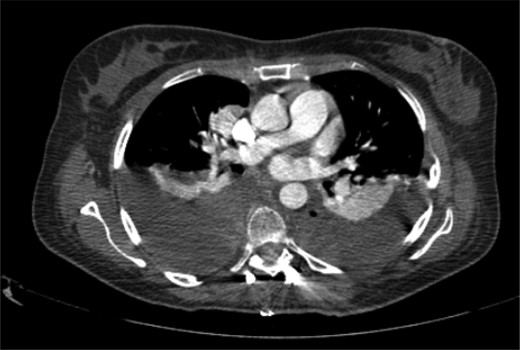

Currently, after 9 months from the initial surgery, the patient remains stable and asymptomatic with no evidence of infection or tumor relapse (Fig. 8). The follow-up imaging studies show encouraging evolution without bone graft resorption or failure of the instrumentation (Fig. 9).

CT scan with no evidence of tumor relapse or instrumentation failure.